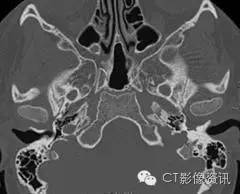

检查所见 CT图像显示明显异常,尽管所示两种异常罕见,但是该异常经常伴随发生。 首先,岩段水平部颈动脉管延长,岩段垂直部缺失。颈动脉自下方扩大的鼓室管进入并穿行中耳。鼓室段颈动脉没有骨质覆盖,并且紧贴鼓膜和听骨链。横断位图像显示出颈动脉狭窄的典型表现。 其次,起源于上颌动脉下颌支的脑膜中动脉需要穿行进入颅内硬膜外间隙的棘孔缺如。而棘孔缺如或者发育不良和第二个诊断直接相关。对CT图像进一步观察发现一个明显的软组织隆起,与右侧不对称,该隆起所在位置恰为面神经走行路径。耳蜗岬细微的侵蚀是该类病变另一种少见的异常,并且由此可能会导致感音神经性耳聋。

最终诊断:颈内动脉变异(左侧)并永存镫骨动脉